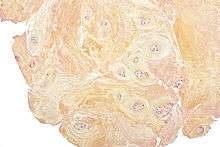

Degenerative discs typically show degenerative fibrocartilage and clusters of chondrocytes, suggestive of repair. Inflammation may or may not be present. Histologic examination of disc fragments resected for presumed DDD is routine to exclude malignancy.

Fibrocartilage replaces the gelatinous mucoid material of the nucleus pulposus as the disc changes with age. There may be splits in the anulus fibrosus, permitting herniation of elements of nucleus pulposus. There may also be shrinkage of the nucleus pulposus that produces prolapse or folding of the anulus fibrosus with secondary osteophyte formation at the margins of the adjacent vertebral body. The pathologic findings in DDD include protrusion, spondylolysis, and/or subluxation of vertebrae (sponylolisthesis) and spinal stenosis.